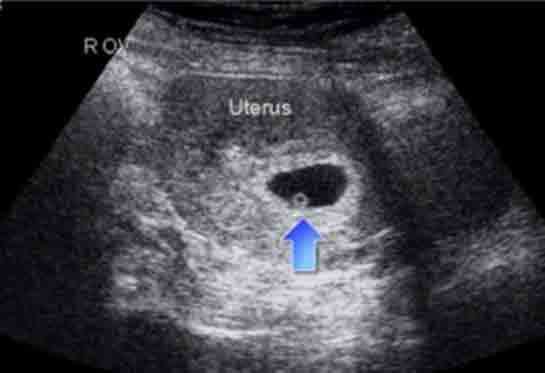

| 36 haftalık gebelik, bir hamilelik sürecinin önemli bir aşamasını temsil eder. Bu dönem, fetüsün gelişiminde kritik bir dönemdir ve anne adayının sağlığı bakımından da dikkate alınması gereken birçok faktör vardır. Bu makalede, 36 haftalık gebelik sürecinin özellikleri, anne adayı ve fetüs üzerindeki etkileri ile birlikte, bu dönemde dikkat edilmesi gereken konular ele alınacaktır. Fetüs Gelişimi 36 haftalık gebelikte fetüs, doğuma oldukça yakın bir dönemde bulunmaktadır. Bu aşamada fetüsün gelişimi ile ilgili bazı önemli noktalar şunlardır: